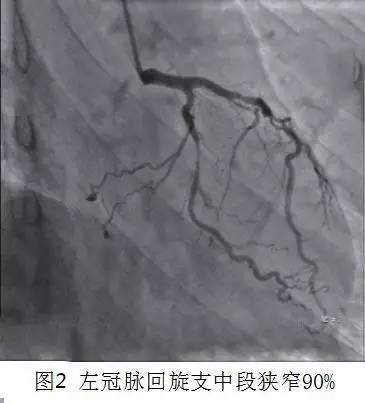

辅助检查:① 颈动脉彩超多普勒示双侧颈总动脉内中膜明显增厚,右侧颈总动脉分叉处后壁及右侧颈内动脉近段前壁多发性粥样斑块;② 运动平板心电图检查报告可疑阳性;③ 冠状动脉造影示左冠前降支开口处、近段、中段弥漫性狭窄,中段于第一间隔支发出后狭窄最重达85%,第一间隔支开口狭窄50%,第二对角支开口处、近段、中段弥漫性病变,回旋支开口狭窄50%,中段不规则病变,狭窄最重达90%(图2),右冠全程弥漫性病变,中段于第一转折处次全闭塞,后三叉前狭窄50%,左室后降支近段闭塞。